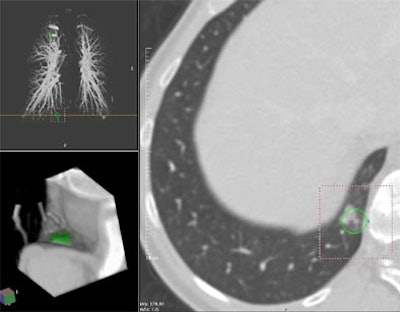

| Contrast enhanced spiral CT for routine follow-up in a 56-year-old woman with a history of breast cancer. Transaxial section at the level of the right phrenico-costal angle. A yellow line indicates the anatomical level of the displayed section within the volume data set in a coronal maximum intensity projection of the pulmonary vascular tree (left upper image panel). An 11-mm, part-solid slightly spiculated soft tissue lung lesion was missed at clinical interpretation but detected by CAD. 3-D volume rendering (left lower image panel) of the lesion highlighted in green displays the anatomic location of the lesion in the dorsal right phrenico-costal recess. Image courtesy of Dr. Joseph Schoepf. |